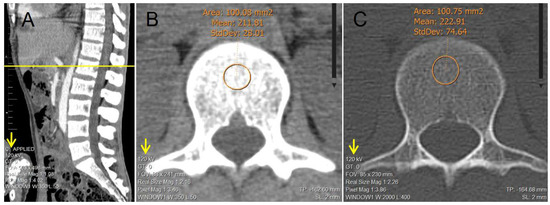

2.2. Image Analysis